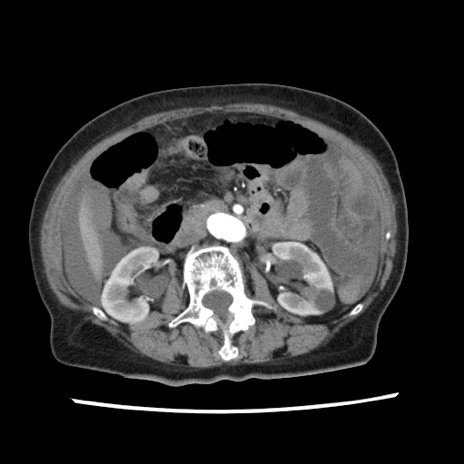

症例1(横断像)

【症例】80歳代女性

【主訴】腹痛

【現病歴】8時間前から腹痛あり来院。

【既往歴】糖尿病、脂質異常症、子宮体癌にて子宮全摘術

【身体所見】意識清明・会話良好だが腹痛で苦悶様、全腹部にわたって反跳痛と圧痛あり

【データ】WBC 13600、CRP 0.14、LDH 224、CK 90